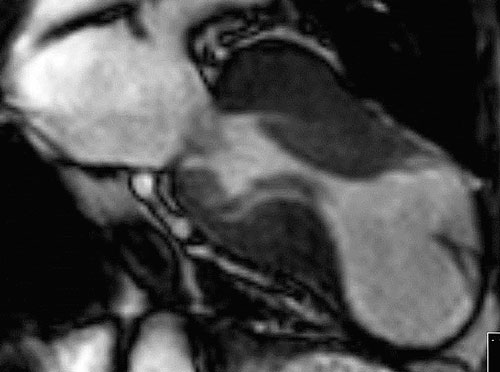

Med magnetkamera kan svårundersökta delar, t ex apex (Figur 6 och 7), och mitralisklaffens funktion ibland bättre bedömas [16]. I riskvärdering för död i arytmi används ibland variablerna sent gadoliniumupptag och förekomst av aneurysm, men kunskapsläget är inte helt klarlagt [17]. Magnetkameran kan bidra till att påvisa inlagringssjukdomar som hjärtamyloidos [18] och Fabrys sjukdom [19].

Figur 6. Magnetkame­ra­undersökning av hjärtat vid apikal hypertrofisk kardiomyopati.

Figur 7. Magnetkameraundersökning av hjärtat visar apikalt aneurysm efter långvarig sjukdom och myektomi.